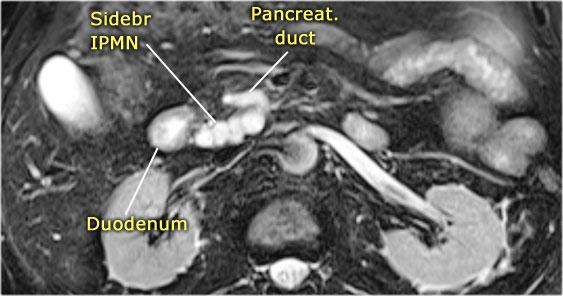

Ở một nam giới 73 tuổi, phát hiện tổn thương giảm âm tại thân tụy, có hình ảnh tương tự tổn thương dạng nang.

CT cũng xác định được tổn thương nhưng không cung cấp thêm nhiều thông tin hữu ích.

Tiếp tục xem hình ảnh MRI.

Chuỗi xung T2W xóa mỡ nặng thể hiện rõ tổn thương đa nang với đường thông thương vào ống tụy.

Trường hợp này được chẩn đoán là IPMN thể ống nhánh.